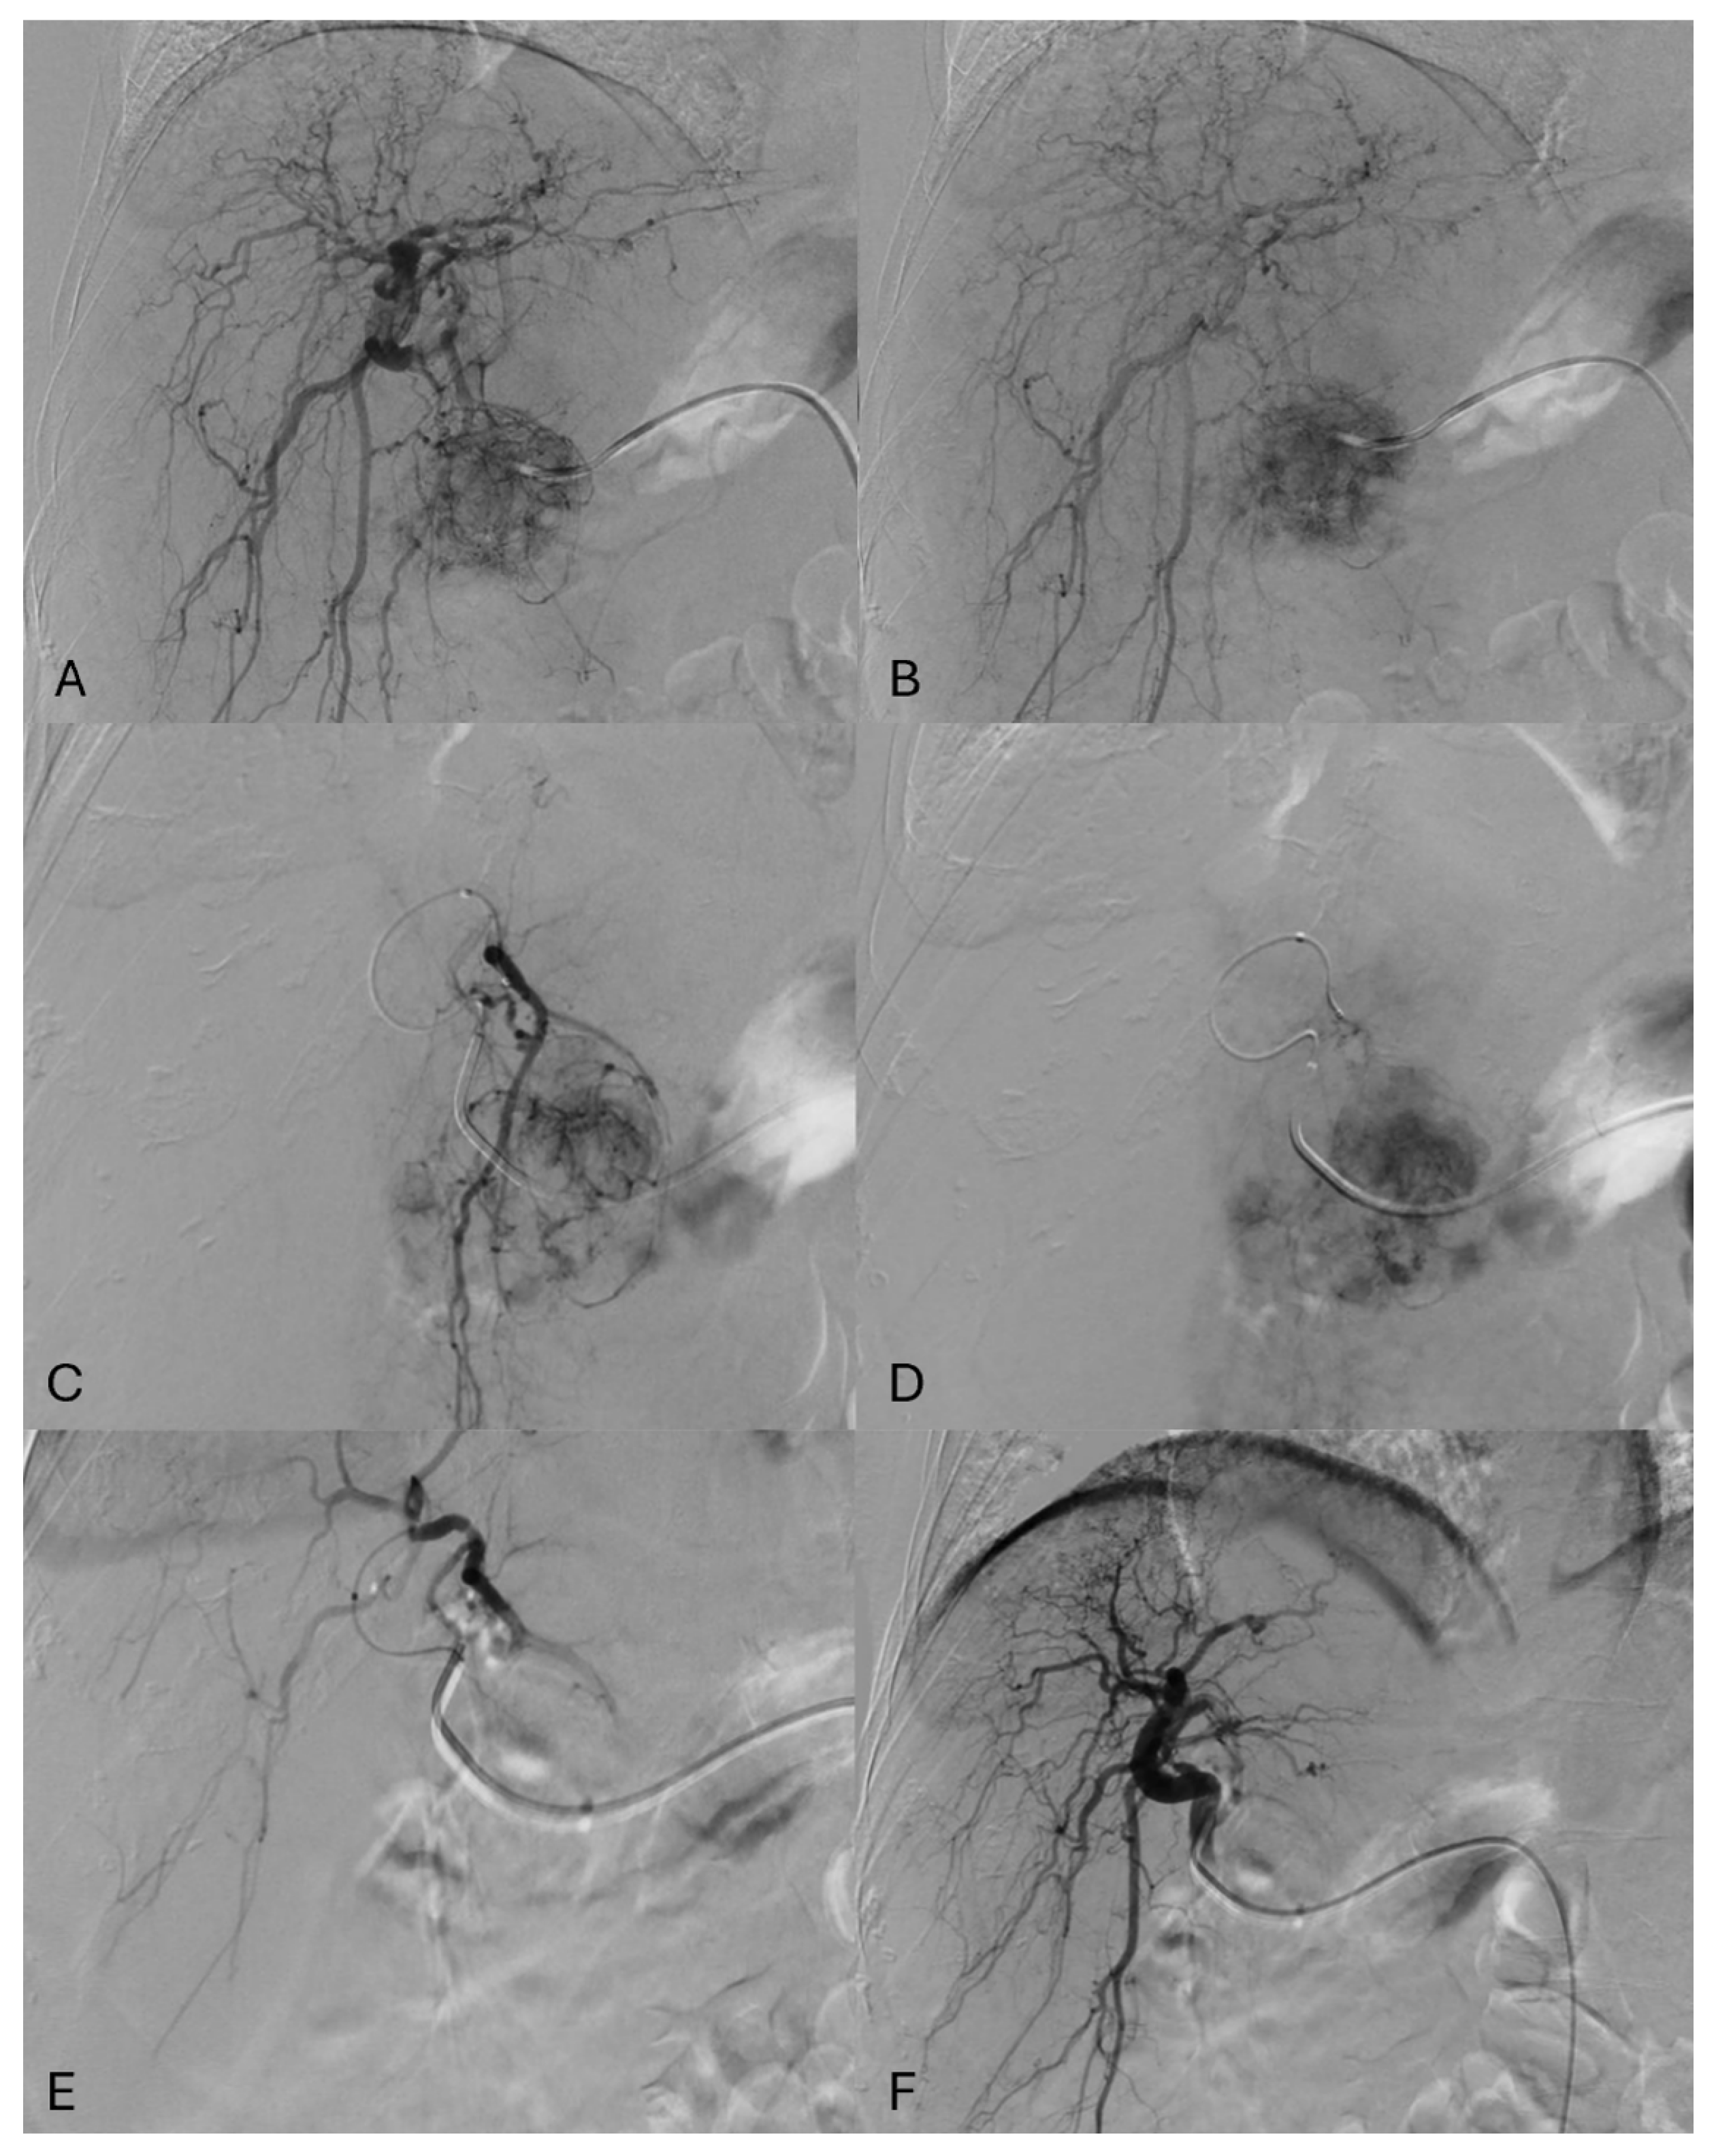

2.1. Procedures’ Protocol

- Castiglione, D.; Galia, M.; Falsaperla, D.; Libra, F.; Basile, A. The “flowering” sign. Abdom. Radiol. 2024, 49, 3294–3296. [Google Scholar] [CrossRef]